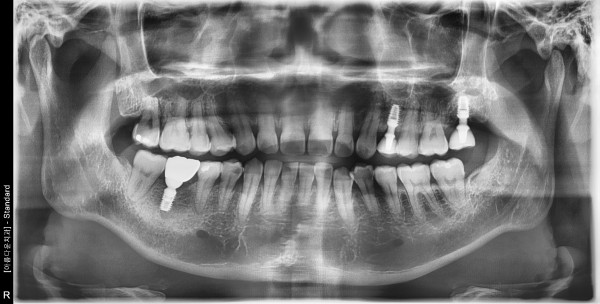

41세남자 상악좌측구치부 하악우측구치부 뼈이식및임플란트식립